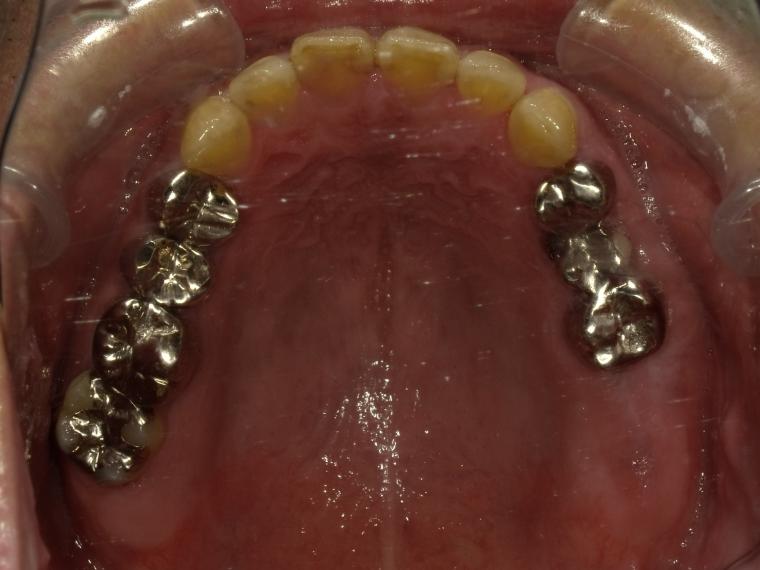

AFTER

41歳男性/上5本欠損/インプラント埋込手術

上5本が虫歯になってしまった為治療をすることになった患者さんです。

虫歯が進行していて、歯を保存出来なかったため歯を抜いて人工の骨を足してからインプラントを

5本埋込した患者さんです。